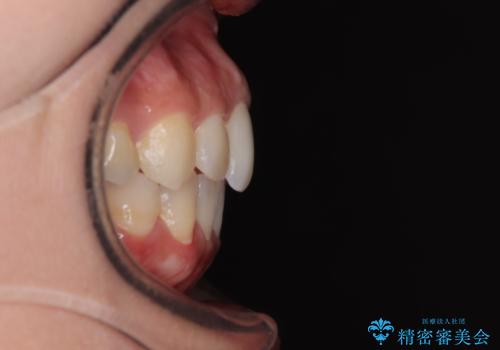

前歯のデコボコを改善 インビザラインの矯正治療

- 前歯のデコボコを治したいとのことで来院された患者様です。

上下顎ともに歯列全体の後方移動とIPR(歯と歯の間を削る)によってデコボコが解消するように設計し、インビザラインにより治療を行うこととしました。